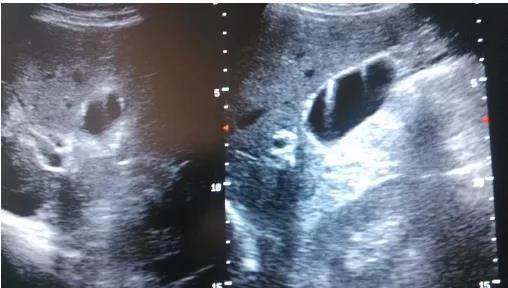

①看真假:真正可能變癌的是真息肉,假息肉不用管;

②看大小:長(zhǎng)到1厘米了就需要考慮手術(shù),風(fēng)險(xiǎn)大了;